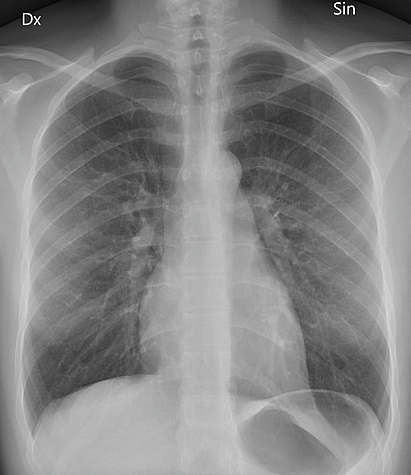

In an X-ray picture bones show as light/white areas, whereas air shows as black or darker areas. The other lighter area in the middle of the image is the heart. The muscle which makes up the heart is also quite dense and stops X-rays passing through.

Radiografía de tórax posteroanterior

By Mikael Häggström (Own work) via Wikimedia Commons